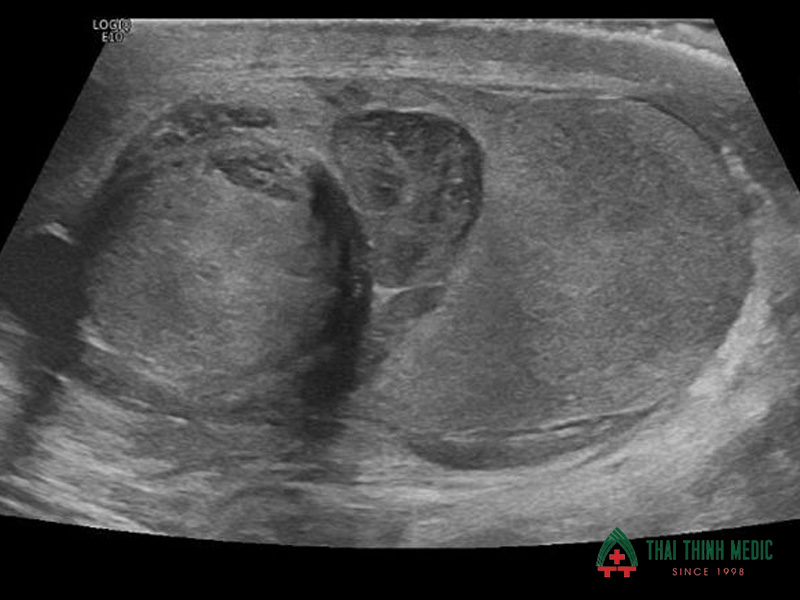

Tràn dịch tinh hoàn

Tràn dịch tinh hoàn là tình trạng tích tụ dịch bất thường quanh tinh hoàn, khiến bìu bị sưng to. Bệnh có thể xuất hiện ở cả trẻ em và người trưởng thành, thường liên quan đến viêm nhiễm hoặc chấn thương vùng bìu.

Siêu âm tinh hoàn giúp xác định lượng dịch trong bìu và đánh giá xem có kèm theo tổn thương khác hay không. Nhờ đó, bác sĩ có thể phân biệt tràn dịch tinh hoàn với các bệnh lý khác như thoát vị bẹn hoặc khối u tinh hoàn.